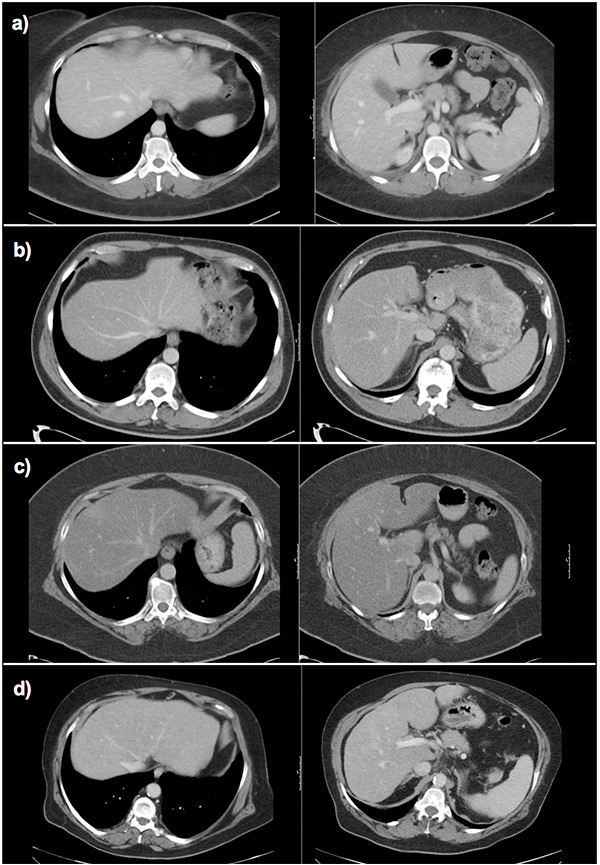

Figure 2

Measurement of the hepatic veins. The three main hepatic veins were measured 1–2 cm before their aperture into the inferior caval vein. Accessory veins were not included. (a) normal liver,(b) liver fibrosis grade 2, (c): liver cirrhosis Child b.

rhv, mhv, lhv = right, middle and left hepatic vein diameters.

Figure 6

Fibrosis assessment with the ld/crl ratio in different patients.

a) Normal liver: wide hepatic veins, caudate lobe smaller than right liver lobe on visual impression. Calculation of the ld/crl-r not mandatory (ld: 2.5 cm, crl-r: 0.75, ld/crl-r: 33.2).

b) Hepatitis C fibrosis grade 1: small hepatic veins, caudate lobe width similar to right hepatic lobe width on visual impression, calculation of the ld/crl-r recommended (ld: 1.5 cm, crl-r: 0.78, ld/crl-r: 19.2).

c) Nonalcoholic steatohepatitis fibrosis grade 1: small hepatic veins, caudate lobe width similar to right hepatic lobe width on visual impression, calculation of the ld/crl-r recommended (ld: 1.6 cm, crl-r: 0.79, ld/crl-r: 20.2).

d) Alcoholic steatohepatitis cirrhosis: very small hepatic veins, caudate lobe width similar to right hepatic lobe width on visual impression, calculation of the ld/crl-r recommended (ld: 1.4 cm, crl-r: 1.1, ld/crl-r: 12.7).

crl-r = caudate-right lobe ratio; ld score = sum of liver vein diameters; ld/crl-r = ld score divided by crl-r